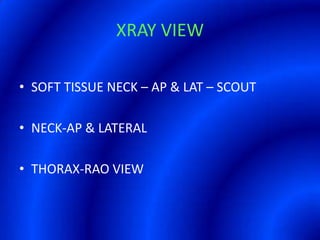

This document provides information about a barium swallow procedure. It begins with an introduction and overview of the embryology and anatomy of the pharynx and esophagus. It then describes the procedure itself, including preparation, technique, views obtained, and indications. Specific conditions that may be examined include pharyngeal and esophageal webs, foreign body impaction, scleroderma, dysphagia, mediastinal masses, and carcinoma. Diagrams are provided to illustrate normal anatomy and various pathological findings.